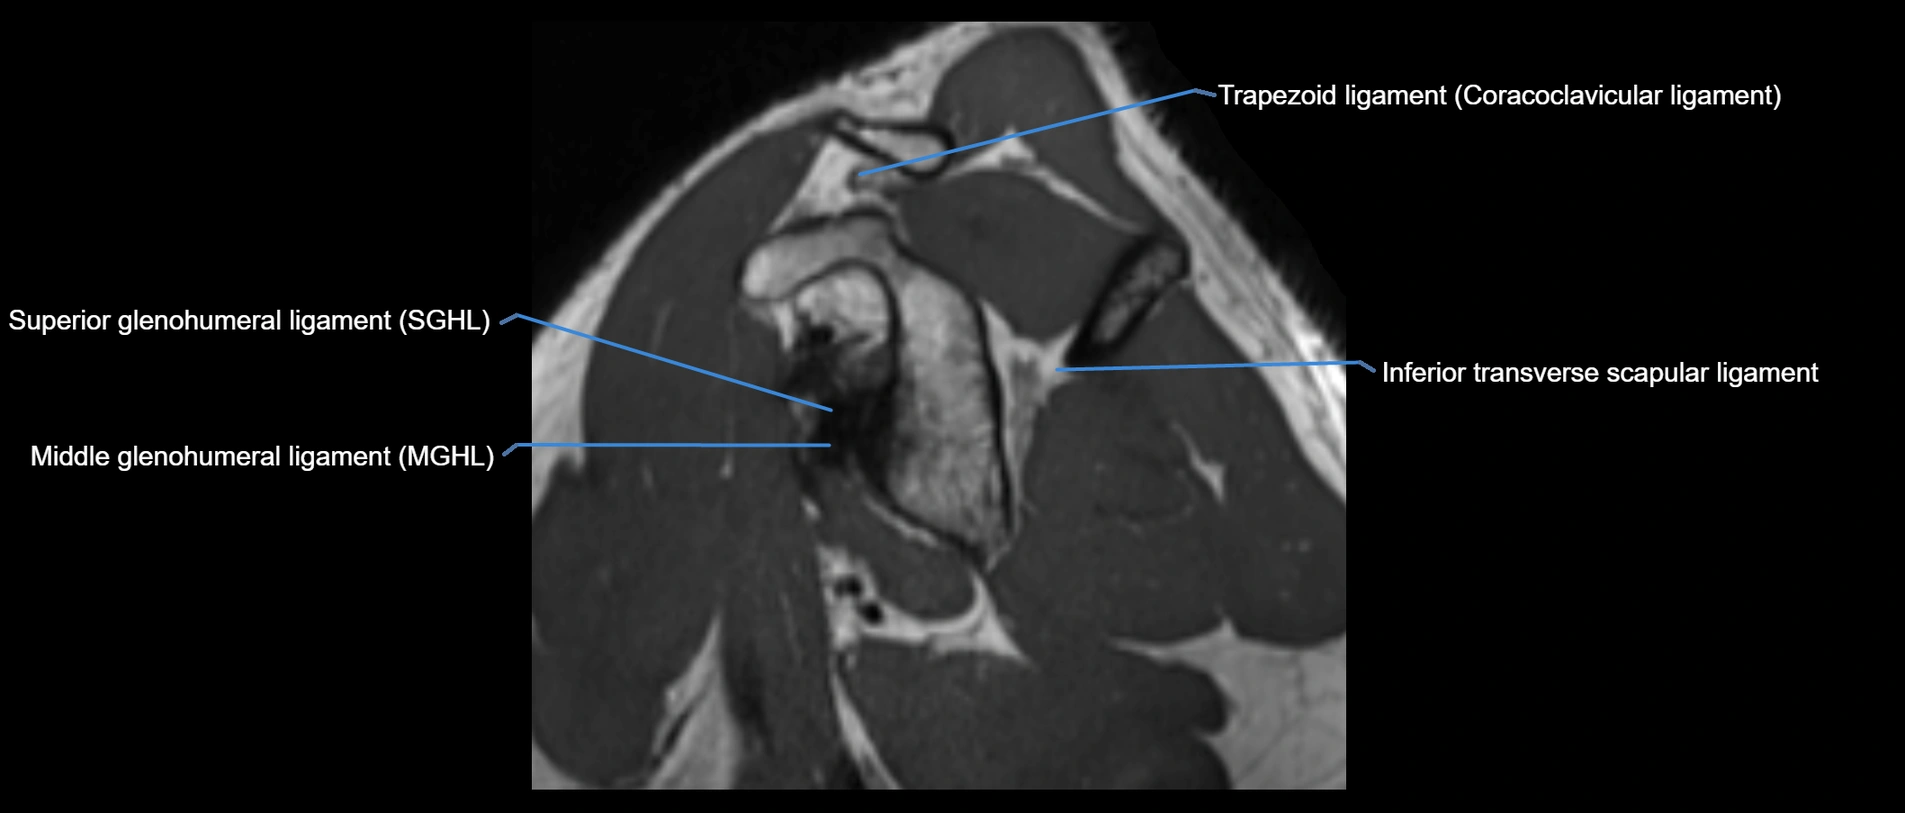

MRI images

image

MRI Appearance

• T1-weighted images:

• Normal ligament: Low signal (dark linear band) spanning acromion to clavicle.

• Surrounding fat planes: Bright, delineating the ligament clearly.

• Marrow of clavicle and acromion: Bright due to fatty content.

• Tears: Discontinuity or irregular thickening with intermediate-to-bright signal.

• Chronic injury: Thinning, fraying, or irregular low-signal fibers with adjacent scarring.

• T2-weighted images:

• Normal ligament: Low signal, homogeneous.

• Partial tear or sprain: Focal hyperintensity or thickening.

• Complete tear: Discontinuity with fluid-bright gap between clavicle and acromion.

• Associated edema: Bright signal in distal clavicle or acromion marrow.